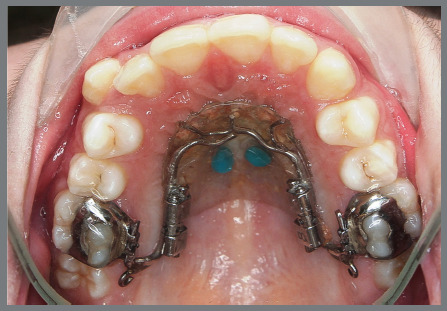

Objective: To assess the effectiveness of a customized distalizer with Variety SP® screws anchored on palatal miniscrews for upper molar distalization.

Methods: Seventeen patients aged between 12.5 and 24 years underwent distalization with a customized distalizer. Lateral cephalogram and cast analysis were performed before and after distalization. Linear and angular parameters of the upper first molar, first premolar, and central incisor were assessed.

Conclusion: The study successfully demonstrated the efficiency of molar distalization without anchorage loss using a customized distalizer anchored on palatal miniscrews.